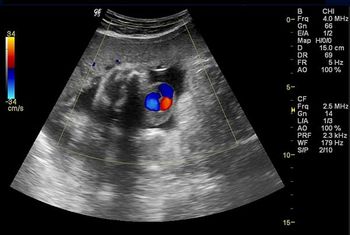

What is your diagnosis in this woman who presents with right hemipelvis pain?